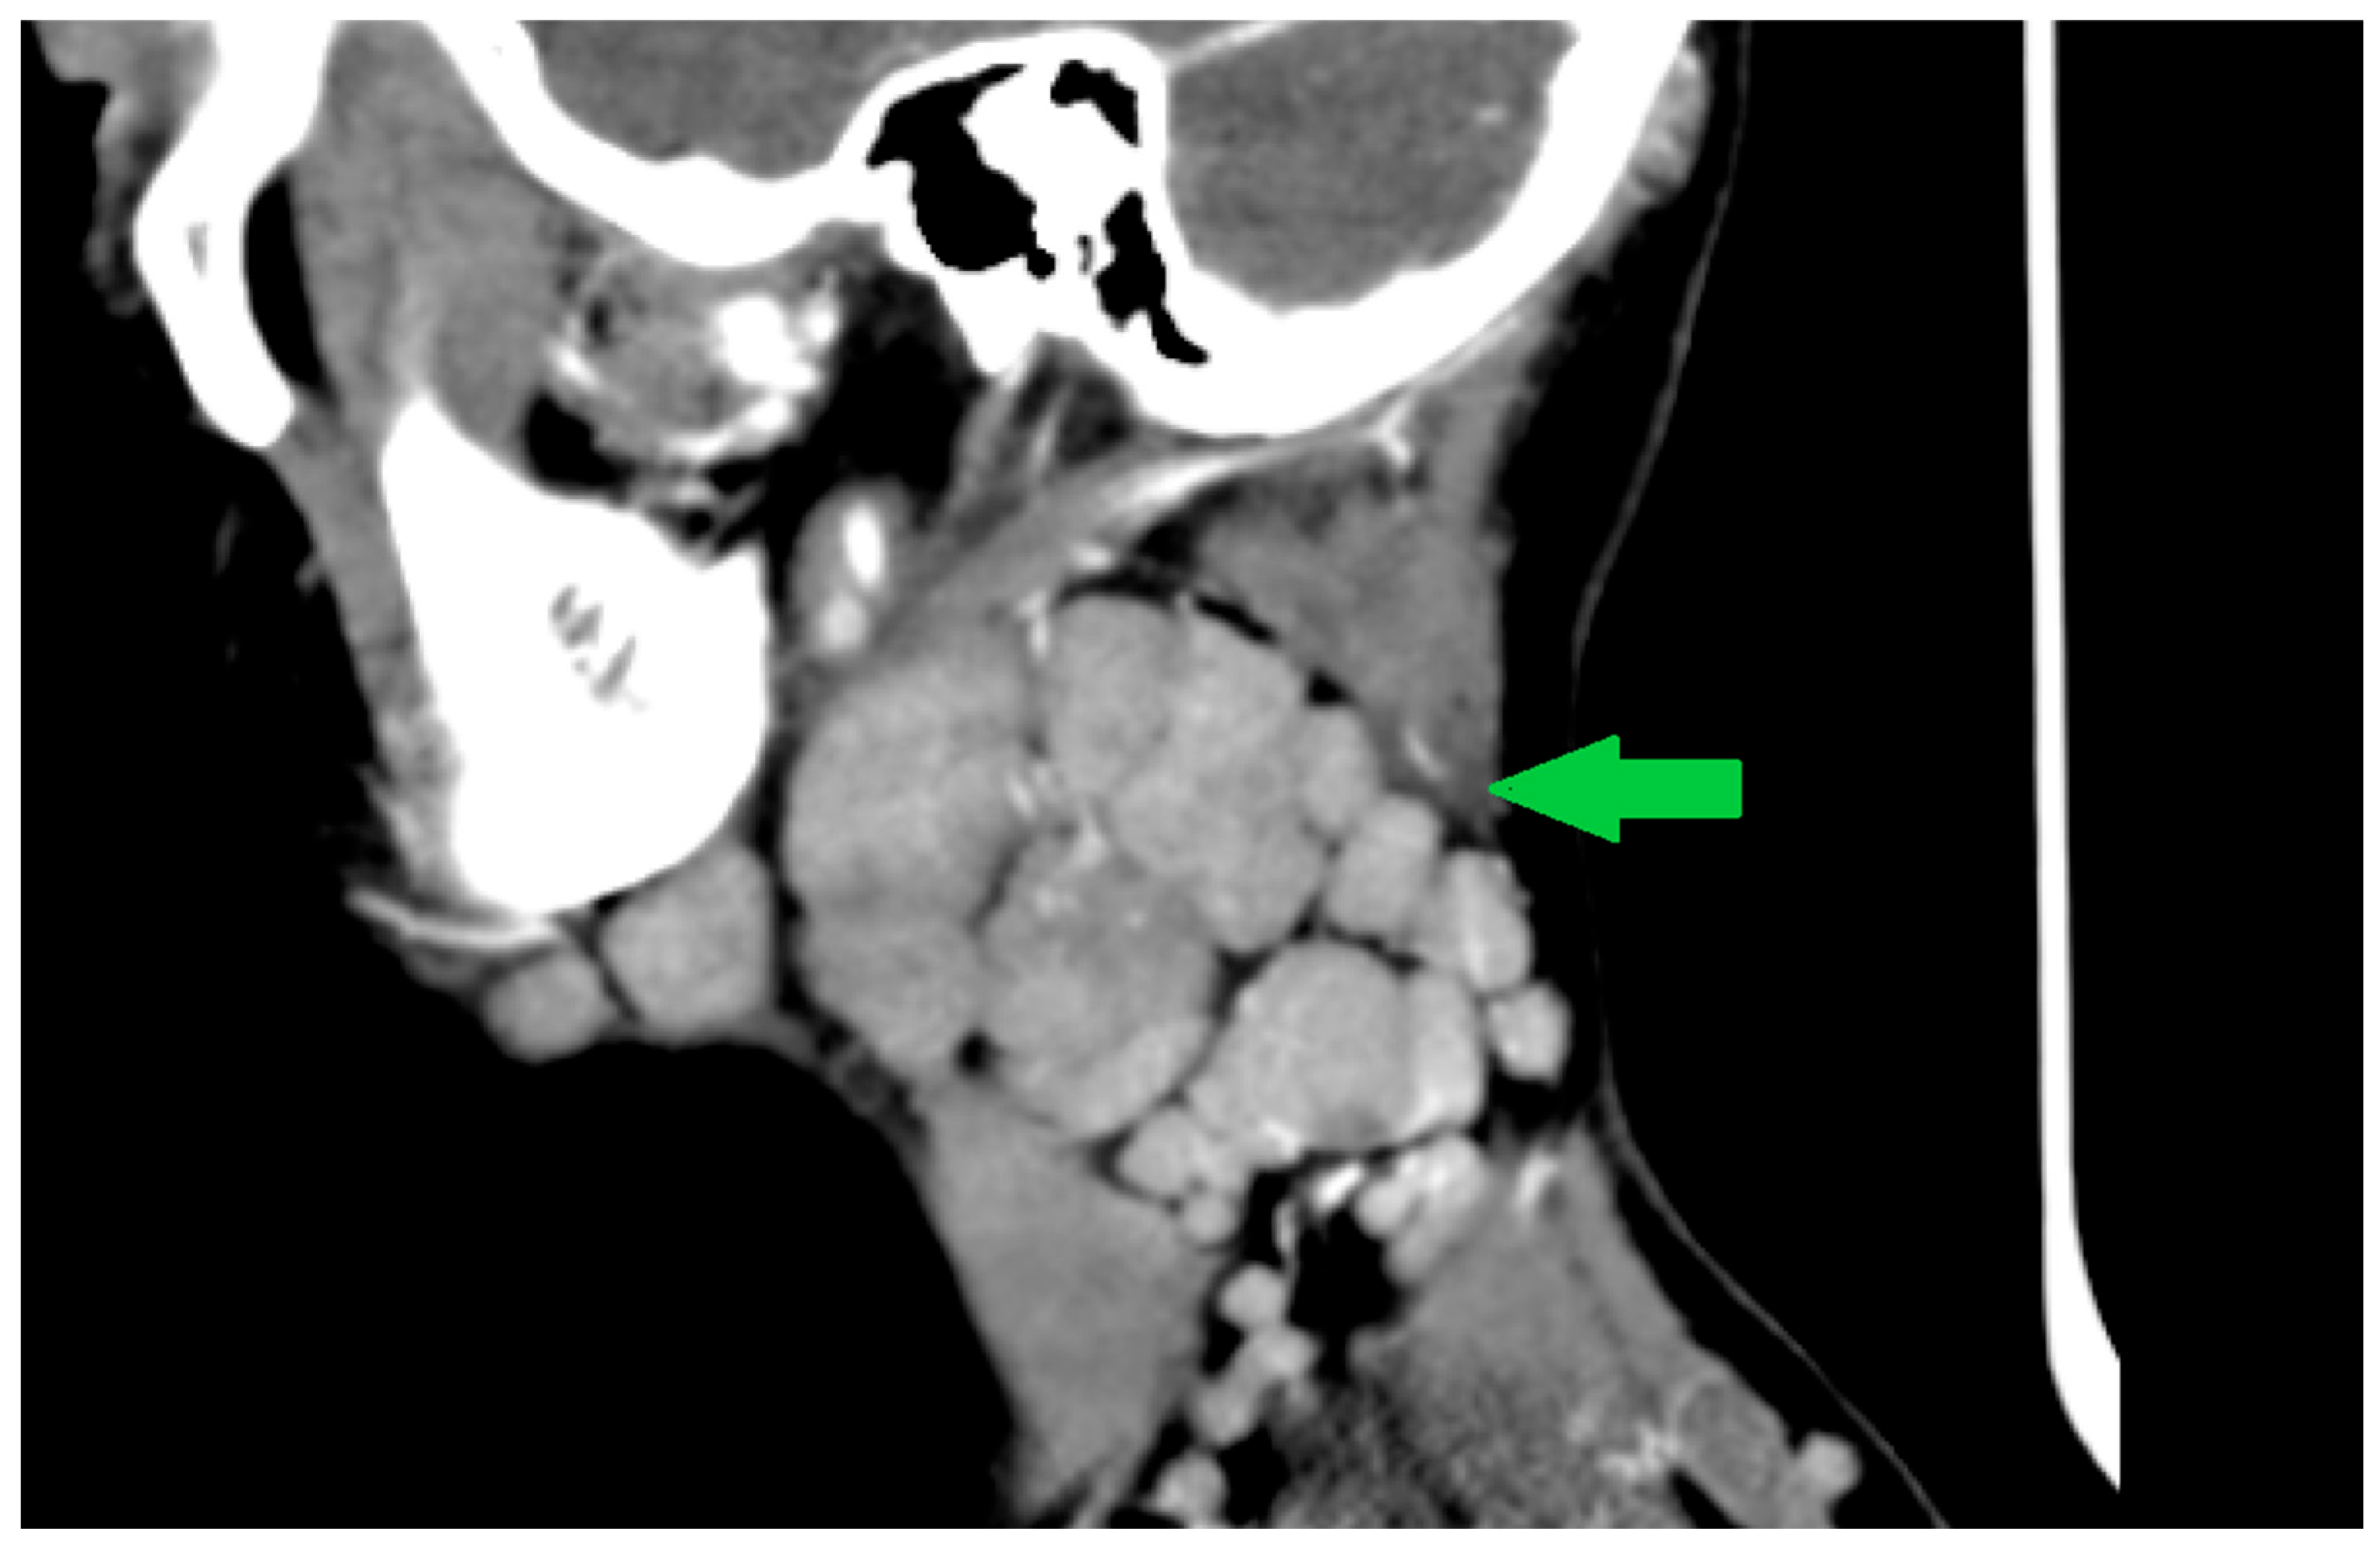

2.1. Case 1